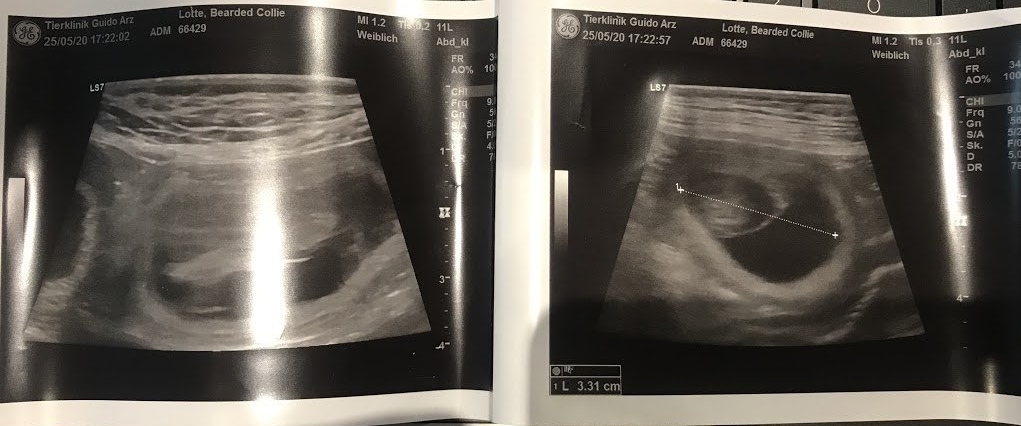

Lotte is pregnant.....we have suspected it for a long time. She didn't eat and felt nauseous...actually all the signs apply to her.

Our vet was so happy for us... I said to her and Clooney no more than 5 puppies but they didn't listen to me... According to the vet she is "full" 🤦♀️.

I hope there aren't too many.

We are so happy.....our Mathilda is expecting puppies around Valentine's Day. We got the confirmation today.....actually you could already guess it. Mathilda was so cuddly and clingy... she doesn't feel like playing, eats badly and has the typical morning sickness. As always, she was very good at the ultrasound. Now we can start with the preparations for the stork. 😍